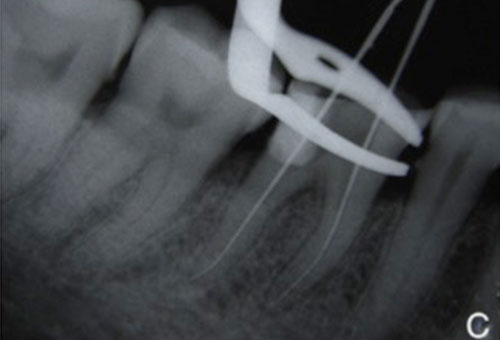

Working length radiograph